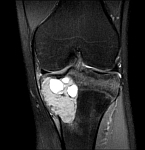

- Tumor surgery of the musculoskeletal system

- Resection of benign and malignant tumors of the bone and soft tissue

- Reconstruction of bone defects by biological procedures (from spongiosaplasty to bone transfer)